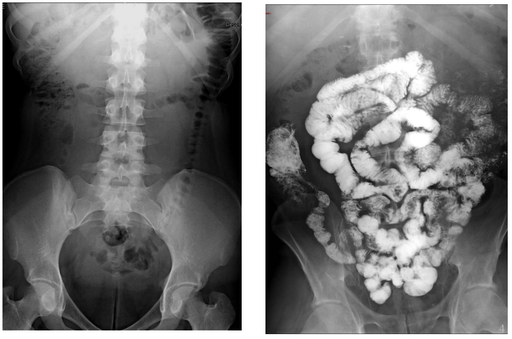

Cancers colo-rectaux

DANSE E. - UCL

Digestif MASTER 1

Contraste digestif en radiologie adulte